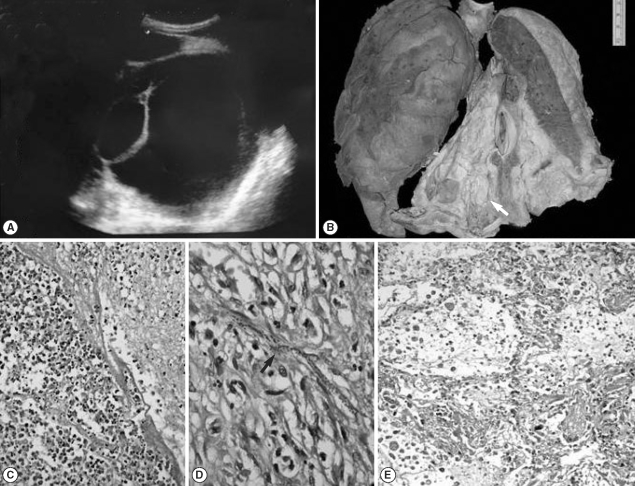

The size and weight of both testes was normal. The spermatic cords were firm in consistency with presence of tiny, whitish nodules (1-2 mm) along its length (Fig. 2A). Microscopically, multiple calcified and hyalinized granulomas were noted around a dead filarial worm with eosinophil rich inflammatory infiltrates. A live adult gravid female worm was also noted within dilated lymphatic vessels (Fig. 2C). The rest of the testicular parenchyma was normal. The liver was enlarged, firm in consistency, and weighed 1,100 g. On microscopy there was evidence of centrizonal sinusoidal dilatation and focal hepatocytic necrosis with presence of microfilariae within the centre of these necrotic foci (Fig. 2D). The spleen weighed 110 g, and on microscopy it showed presence of ill-formed granulomas and eosinophilic microabscesses around microfilariae. The kidneys weighed 280 g and were normal in size. Many glomerular capillaries showed presence of fibrin thrombi along with many microfilariae (Fig. 2E). Few glomeruli also revealed necrotizing lesions. The interstitium showed eosinophilic microabscesses with microfilariae. The heart weighed 250 g, and there were features of chronic rheumatic valvulitis with thickened, stenotic mitral valve leaflets, chordate, and commissural fusion. Also tiny verrucous vegetations (1-2 mm) were noted on the atrial aspect of the mitral valve along the line of closure of the leaflet. On microscopic examination, the vegetations were confirmed to be non-bacterial in origin. Features of eosinophilic hypersensitive myocarditis with patchy endomyocardial fibrosis (EMF), secondary to hypereosinophilia, were noted in the ventricular myocardium.